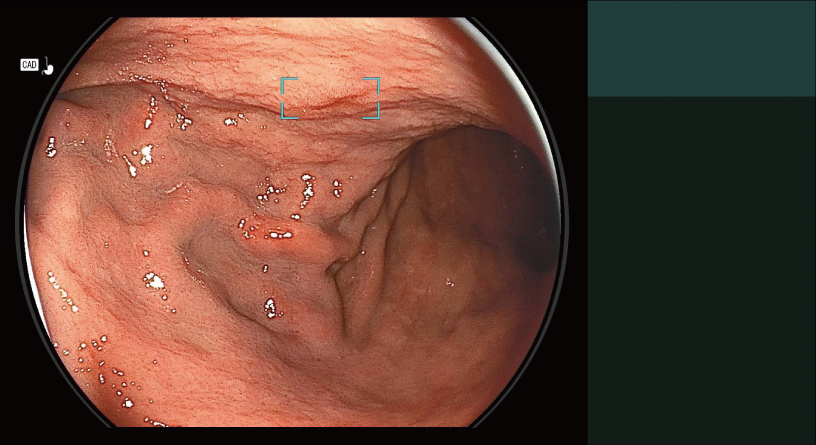

Detects the area that may be gastric neoplastic lesion and displays it on the main monitor in real-time.

Detection Box

Indicates the area where this software suspects that a lesion is present.

The types of Detection Mode are automatically switched depending on the observation mode selected.

- *1 Detection Mode for Gastric Neoplastic Lesion Suspect Area